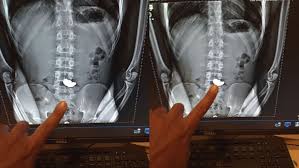

Ele foi levado ao Hospital Odilon Behrens, na região Noroeste da capital, onde um exame de raio-X confirmou a presença da corrente de ouro no estômago.